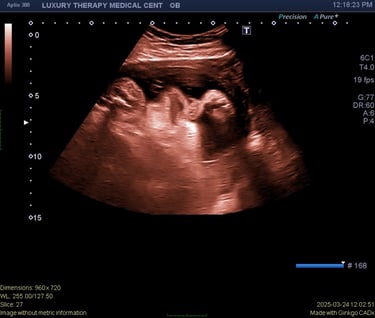

A complete obstetric ultrasound is a detailed imaging exam used to evaluate the baby and the uterus during pregnancy. This ultrasound helps healthcare providers assess fetal development and identify important pregnancy milestones.

A complete OB ultrasound may evaluate:

Fetal growth and development

Fetal heartbeat

Gestational age

Position of the baby

Placenta location

Amniotic fluid levels

This examination provides important information about the progress of the pregnancy.

Ultrasound images of the uterus and baby are obtained

Measurements of fetal growth may be taken

The baby’s position and development are evaluated